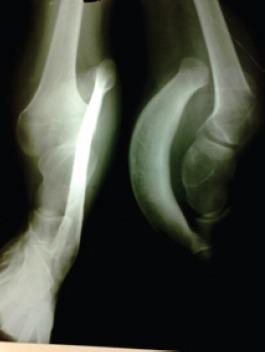

We present a 17-year-old girl having mirror foot with dysplastic trapezoid shaped tibia. She had mild equinovarus deformity of the right foot with three pre-axial extra digits that represent a mirror foot. There was also a gross shortening of the right leg with 20° fixed flexion deformity of the knee, but she could walk around with limited disability. Her chief complaint was difficulty in outdoor ambulation and poor cosmesis of the foot. Limb reconstruction may not have a predictable outcome with so much of shortening and she was also reluctant for amputation. A course of therapy was given with a treatment objective of improvement of knee flexion deformity and quadriceps control. She was fitted with an extension prosthesis which accommodates the deformed foot and also corrected the limb length discrepancy.

我们报告一名17岁女孩,患有镜像足及发育异常的梯形胫骨。她右足有轻度马蹄内翻畸形,伴有三个轴前额外趾,构成镜像足。右腿明显短缩,膝关节有20°固定屈曲畸形,但她仍能有限度地行走,残疾程度较轻。她的主要诉求是户外行走困难以及足部外观不佳。鉴于有如此严重的短缩情况,肢体重建可能无法取得可预测的结果,而且她也不愿接受截肢。给予了一个疗程的治疗,目标是改善膝关节屈曲畸形并增强股四头肌控制能力。为她安装了一个可容纳畸形足并矫正肢体长度差异的延长假体。